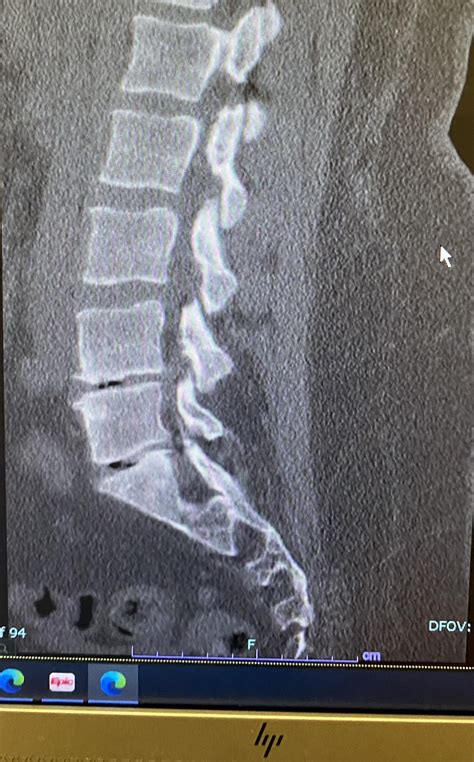

• Imaging Tests: X-rays, MRI, or CT scans can provide detailed images of the spine, helping to identify any abnormalities or damage to the L5 S1 disc.